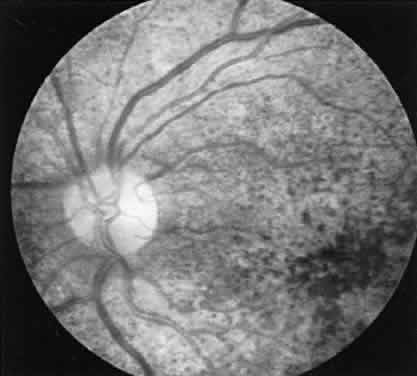

The physician who deals with a hereditary problem becomes the first line in genetic counseling. Making the correct diagnosis is the initial step, but it is likewise important to ascertain, as far as possible, the hereditary mode of the disease. In the case of retinitis pigmentosa, where all three modes of inheritance are seen, the importance becomes obvious with regard to future generations. If an individual is seen without a positive family history, autosomal recessive is statistically the most likely mode of inheritance.11 But if one further considers an isolated case of a male presenting with such a problem, the possible diagnosis of X-linked recessive retinitis pigmentosa cannot be ruled out. In such a case it is important to examine any female who might be the carrier of the X-linked gene. In a large percentage of such cases the female carrier shows fundus changes in the absence of any subjective complaints.12 These may consist of an unusual scintillating reflex in the macular area or a clumping of pigment in the periphery (Fig. 13). However, these changes are not always seen. In such cases electrophysiologic studies provide the answer, for it has been found that certain electrophysiologic abnormalities also are seen in the majority of female carriers, even those with no fundus abnormalities. These consist of a prolonged photopic b-wave implicit time and/or a reduction in the amplitude of the scotopic b-wave in a fully dark-adapted eye.13

Fig. 13. Female carrier of X-linked retinitis pigmentosa. Fundus photographs of a 48-year-old female with vision of 20/20 OD and OS. Left. Macular area shows an unusual scintillating reflex around the entire parafoveal region. Right. Retinal periphery showing an isolated area of retinal pigment epithelial loss with associated clumps of pigment.